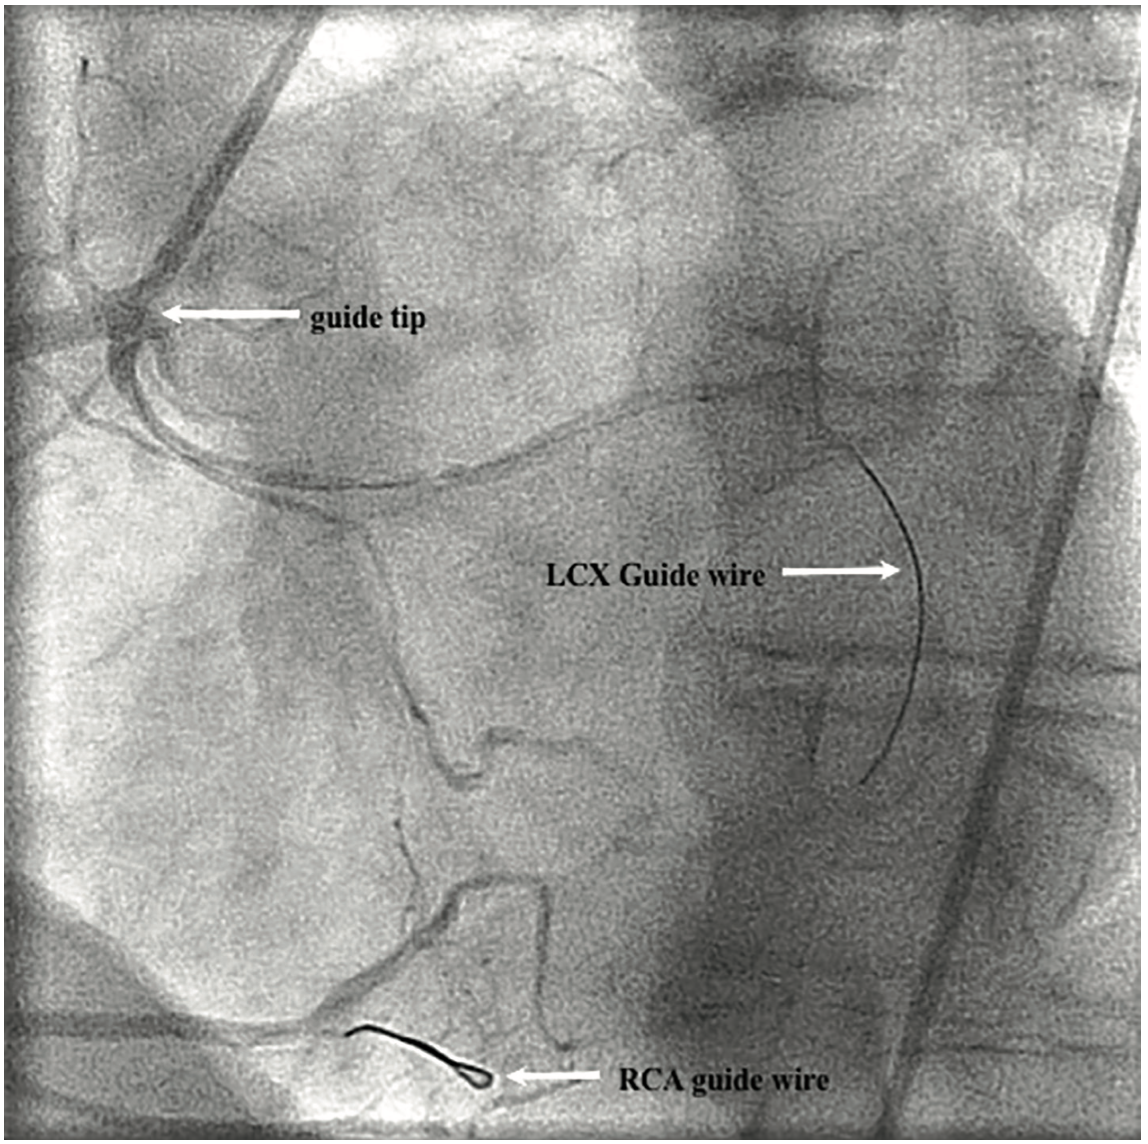

Figure 3. MP2 catheter deeply intubating the RCA and the first BMW wire in the distal RCA with a knuckle tip.

Figure 4. “Push the knuckle” technique retracts the guide tip, allowing for passage of a second BMW wire into the LCX.

Figure 2. Left anterior oblique (LAO) projection: Patent right coronary artery (RCA) and LCX seen originating from main RCA.

A 56-year-old male presented with unstable angina pectoris. He had known severe anomalous LCX disease managed medically thus far. Past medical history was also significant for hypertension, hyperlipidemia, and diabetes. Cardiovascular physical examination was unremarkable. An electrocardiogram (EKG) showed sinus bradycardia and diffuse, mild ST segment elevations. An echocardiogram showed normal left ventricular systolic function and no pericardial effusion. Troponin I level was initially normal. The patient was treated with heparin, nitroglycerin, beta-blocker, statin, and aspirin. Coronary angiography showed non-obstructive disease in the left anterior descending artery (LAD); the LCX was not visualized on the left system injection (Figure 1 shows the right anterior oblique [RAO] caudal projection). The RCA was dominant with normal take-off and no obstructive disease noted; however, the LCX was seen coming off the proximal part of RCA, and was noted to be severely and diffusely diseased. The mid LCX had a 95-99% stenosis and distal segments with less severe but also obstructive disease in the proximal portion (Figure 2 is the left anterior oblique [LAO] straight projection). The LCX had a culprit lesion that we decided to stent. A 6 French multipurpose guide catheter (Multipurpose [MP] 2 [Boston Scientific]) was inserted via right femoral artery access. This catheter has a tendency for deep intubation of the RCA (Figure 3). In order to avoid an unfavorable prolapse into the take-off of the LCX on pullback (there is a right angle between the proximal LCX and the guide, thus increasing the risk of LCX guide dissection), a Balance Middleweight (BMW) guide wire (Abbott Vascular) was placed into the distal RCA branch. Its distal end was looped (into a “knuckle”). The wire was pushed forward and in doing so, the guide catheter was pushed in a controllable manner out of the RCA to the level of the LCX take-off. Once at this level, the LCX was wired with another BMW guide wire (Figure 4). The LCX was predilated with a 2.0 x 15 mm balloon and then stented with a Xience Prime 2.75 x 38 mm stent (Abbott Vascular) (distal and mid portions) and 2.75 x 18 mm (proximal) stents at high pressure. The result was satisfactory (Figure 5, Video 1).